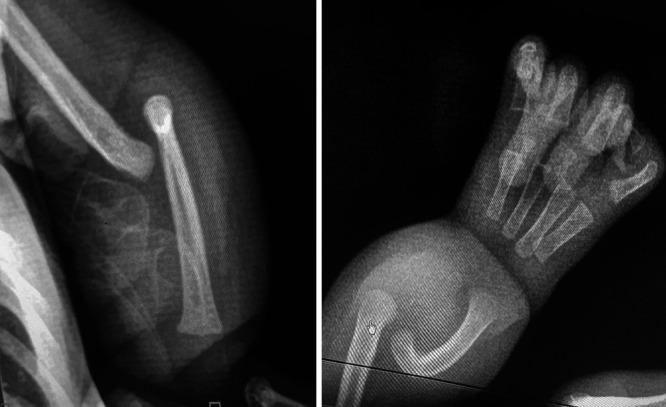

The authors present the case of a 3-month-old male with low-back swelling that was off-center to the left, accompanied by a left short forearm displaying outward bowing. Echocardiography showed an atrial septal defect. This rare VACTERL association comprises lipomyelomeningocele, atrial septal defect, and ulnar longitudinal deficiency syndrome. During surgical intervention for the lipoma, a well-defined cartilaginous mass was discovered within the adipose tissue.

作者报告了一例3个月大男性病例,其下背部左侧有偏中心肿胀,伴有左侧前臂短小并向外弯曲。超声心动图显示房间隔缺损。这种罕见的VACTERL综合征包括脂肪脊髓脊膜膨出、房间隔缺损和尺骨纵向发育不全综合征。在对脂肪瘤进行手术干预时,在脂肪组织内发现了一个边界清晰的软骨块。